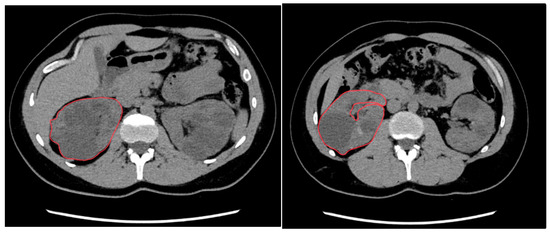

2.3. Manual Segmentation